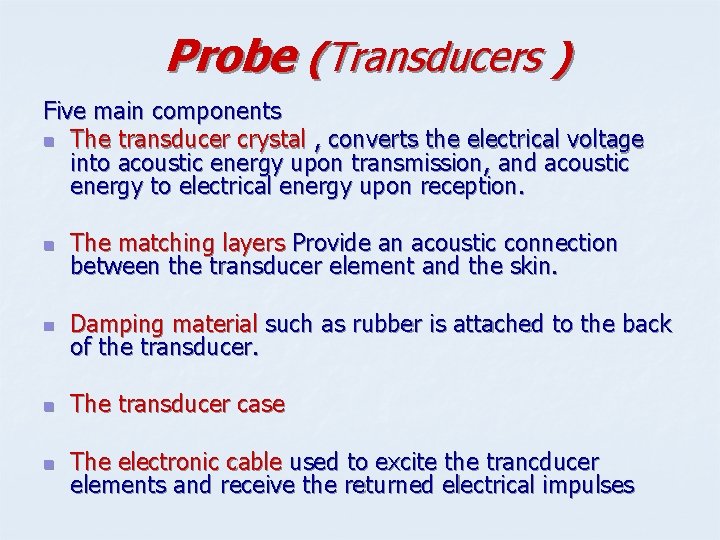

Probe (Transducers ) Five main components n The transducer crystal , converts the electrical voltage into acoustic energy upon transmission, and acoustic energy to electrical energy upon reception. n The matching layers Provide an acoustic connection between the transducer element and the skin. n Damping material such as rubber is attached to the back of the transducer. n The transducer case n The electronic cable used to excite the trancducer elements and receive the returned electrical impulses